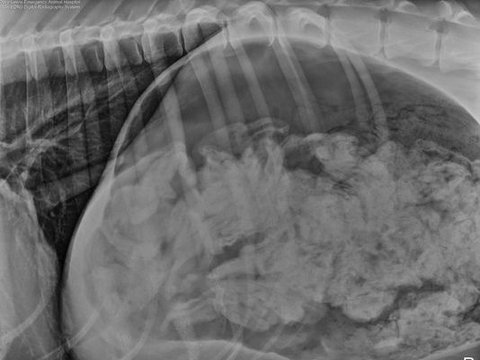

개 위속에서 양말 43개가 나옴

개가 아파서 병원에 데려갔는데

x레이에 이상한게 찍힘

수술하려고 개복하니

양말 43개와

반쪼가리였는데 모양 색깔 다 달랐다고 함

개이름은 Great Dane 이고 세살이라고 함

수술후 다행히 괜찮아졌다고 하네요